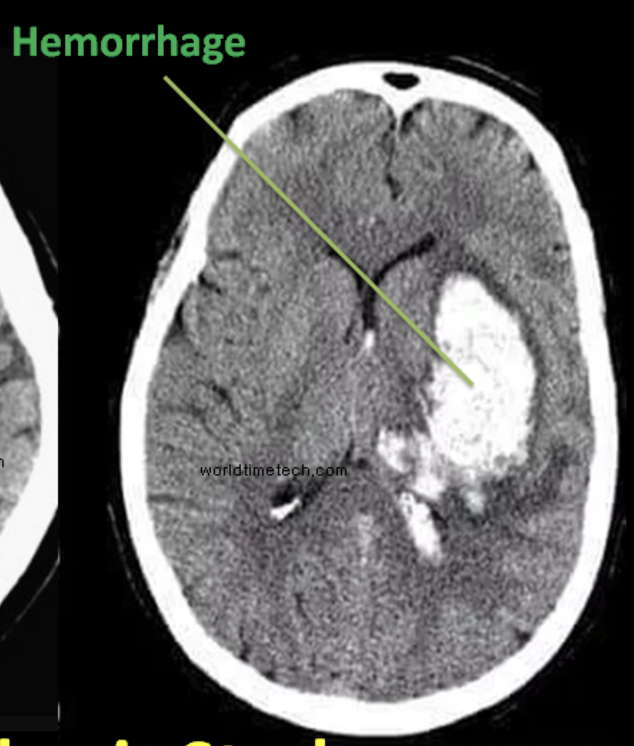

Recurrent epistaxis + AVM + telangiectasia: - Osler-Weber-Rendu Syndrome (aka Hereditary Hemorrhagic Telangiectasia) HY Assoc: Can result in cerebral AVM --> hemorrhagic strokes or - Cerebral abscesses due to venous blood bypassing Pulm circulation if there's a pulmonary AVM!